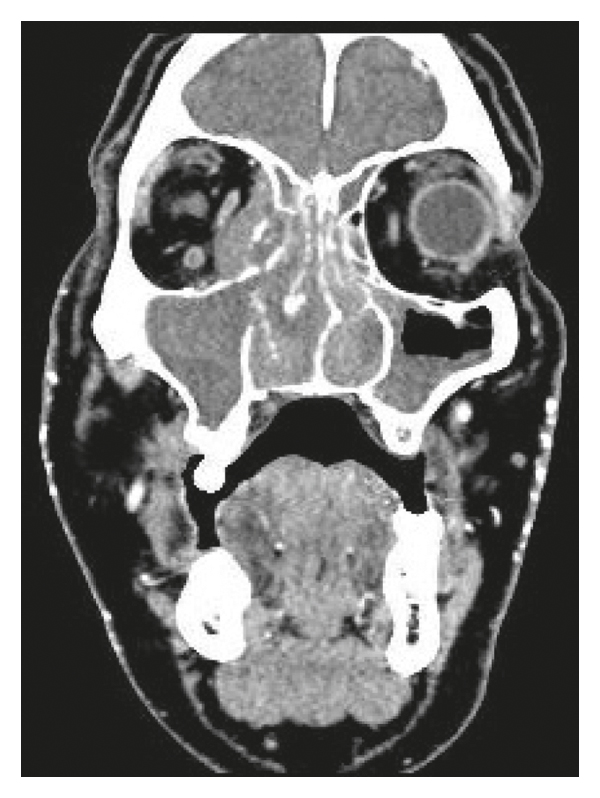

A 44-year-old Hispanic male from Mexico presented to the emergency department for progressive nasal congestion, rhinorrhea, ear fullness, facial swelling, and sore throat that has been ongoing for 2 months. He also noted gradual vision loss of his right eye and intermittent bloody discharge from both the nostrils. Bedsides, rhinoscopy showed swelling of the right nare and nasal turbinates along with small blood clots without active bleeding. A maxillofacial computed tomography (CT) scan showed phlegmonous change about the right lamina papyracea with an erosive change. Also shown was destruction and soft-tissue swelling that extends along the medial border of the right orbit (Figure 1). Biopsy of the right nasal vestibule was diagnostic for extranodal NK/T-cell lymphoma nasal type. The atypical cells were positive for CD2, CD3, CD4, CD56, CD43, and Bcl-2 and negative for CD5, CD7, CD8, CD10, CD20, CD30, and BCL-6. In situ hybridization was positive for the Epstein–Barr encoding region (EBER). Bone marrow biopsy showed a normocellular bone marrow with trilineage hematopoiesis. Additional imaging with magnetic resonance imaging (MRI) of the head showed a vague enhancement over the frontal convexities. EBV DNA PCR in the blood was 4.90 log10 IU/mL (equivalent to 79,792 IU/mL). He was started on a modified SMILE (m-SMILE) regimen consistent of methotrexate 2 g/m2 given on day 1, etoposide 100 mg/m2, ifosfamide 1500 mg/m2, dexamethasone 40 mg/d given on days 2 to 4, and pegasparagase 2000 U/m2 given on day 8 of a 28-day cycle (Figure 2). He developed acute right-sided complete vision loss; magnetic resonance imaging of the orbits showed increased enhancement of the optic nerve sheath with a complex edema suspicious for optic nerve invasion. The case was discussed at an ENT oncology and other multidisciplinary oncology conferences; the decision was made to proceed with the same chemotherapy regimen. The patient then received prophylactic intravitreal methotrexate of the left eye. He completed his second cycle of m-SMILE, and a follow-up positron emission tomography-computed tomography (PET/CT) scan showed good response (Figure 3(a)). Methotrexate dose had to be reduced 50% on the third cycle of m-SMILE due to kidney injury. He subsequently received 4 more cycles of m-SMILE with 25% dose reduction of chemotherapeutic agents due to prolonged cytopenia from previous cycles. His EBV DNA PCR turned undetectable after the first cycle and remained so after the final (6th) cycle. A restaging PET/CT scan showed good response with faint residual disease in the paranasal sinuses and sinonasal cavity (Figure 3(b)). One month after he completed his last cycle, he developed new-onset severe headache, confusion, and shortness of breath. He was admitted to the emergency department where a CT scan of the head showed diffuse cerebral and cerebella edema. MRI of the brain with intravenous contrast revealed multiple focal cortical and subcortical signal abnormalities, with extensive gyral swelling involving the frontal, anterior parietal, and bilateral temporal lobe. Subtle enhancement in the sulci of the high frontoparietal region, particularly at the central sulcus, was noted (Figures 4 and 5 ). Cerebrospinal fluid examination was positive for CD 56+ cells and aberrant atypical lymphocytes. EBV DNA PCR was 14,800 IU/mL. His course was later complicated by respiratory failure and cerebellar tonsillar herniation; he subsequently succumbed after 19 days of hospitalization.